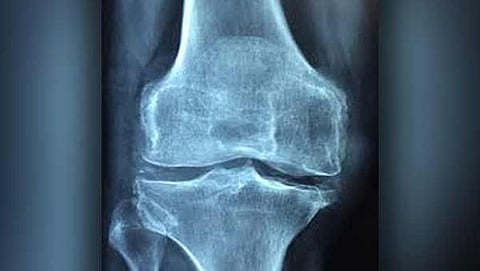

ವಾಷಿಂಗ್ ಟನ್: ಆಸ್ಟಿಯೊಪೊರೋಸಿಸ್‌ (ಅಸ್ಥಿರಂಧ್ರತೆ) ಎಂಬ ಮೂಳೆಗಳಿಗೆ ಸಂಬಂಧಿಸಿದ ಸಮಸ್ಯೆಗೆ ಚೀನಾದ ಗಿಡಮೂಲಿಕೆಯಲ್ಲಿ ಮದ್ದು ಇದೆ ಎಂದು ಕೆನಡಾದ ಸಂಶೋಧಕರು ಹೇಳಿದ್ದಾರೆ.

ಯಾವುದೇ ಅಡ್ಡ ಪರಿಣಾಮಗಳಿಲ್ಲದೇ ಚೀನಾದಲ್ಲಿ ಬಳಕೆಯಾಗುವ ಸಾಂಪ್ರದಾಯಿಕ ಔಷಧ ಆಸ್ಟಿಯೊಪೊರೋಸಿಸ್‌ ಸಮಸ್ಯೆಯನ್ನು ನಿವಾರಿಸುವ ಸಾಮರ್ಥ್ಯ ಹೊಂದಿದೆ. ಅಷ್ಟೇ ಅಲ್ಲದೇ ಮೂಳೆಗಳನ್ನು ಶೇ.35 ರಷ್ಟು ಸದೃಢಗೊಳಿಸಬಲ್ಲದು ಎಂಬುದನ್ನು ಕೆನಡಾದ ಸಂಶೋಧಕರು ಕಂಡುಕೊಂಡಿದ್ದಾರೆ.

ಕೇವಲ ಆಸ್ಟಿಯೊಪೊರೋಸಿಸ್‌ ಅಷ್ಟೇ ಅಲ್ಲದೇ ಸಂಧಿವಾತ ಮತ್ತು ಕೆಲವು ಮೂಳೆಯ ಕ್ಯಾನ್ಸರ್ ಗಳನ್ನೂ ಸಹ ಈ ಗಿಡಮೂಲಿಕೆಯಿಂದ ಗುಣಪಡಿಸಬಹುದಾಗಿದೆ.  ಕ್ಯಾಥೆಪ್ಸಿನ್ ಎಂದು ಕರೆಯಲಾಗುವ ಕಿಣ್ವ (ಎನ್ಝೈಮ್) ನಿಂದ ಉಂಟಾಗುವ ಸಮಸ್ಯೆಗಳನ್ನು ರೆಡ್ ಸೇಜ್ ಗುಣಪಡಿಸಬಲ್ಲದು ಎಂದು ವ್ಯಾಂಕೋವರ್ನಲ್ಲಿ ಬ್ರಿಟೀಷ್ ಕೊಲಂಬಿಯಾ ವಿಶ್ವವಿದ್ಯಾಲಯದ ಸಂಶೋಧಕರು ಹೇಳಿರುವುದು  ಮೂಳೆ ಮತ್ತು ಖನಿಜ ಸಂಶೋಧನೆಗೆ ಸಂಬಂಧಿಸಿದ ಜರ್ನಲ್ ನಲ್ಲಿ ಪ್ರಕಟವಾಗಿದೆ.